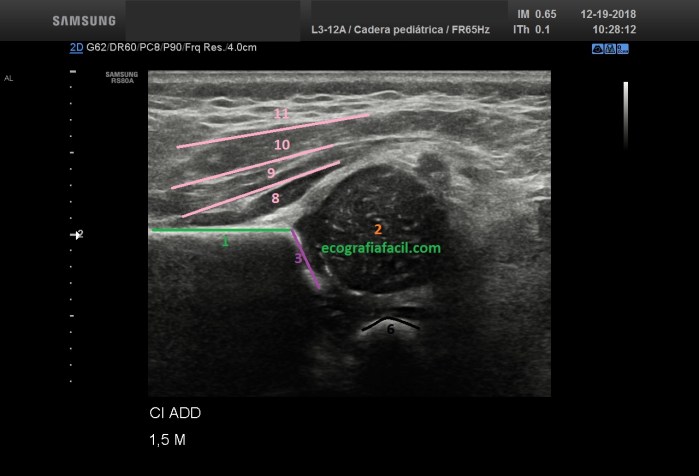

- 1. Iliaco

- 2. Cabeza femoral

- 3. Acetábulo

- 6. Pubis

- 8. Glúteo Menor

- 9. Glúteo mediano

- 10. Tensor de la Fascia lata.

- 11. Tejido celular subcutáneo

Sí me he saltado números, pero son aquellos que he considerado como menos importantes con el fin de facilitarte el aprendizaje de aquellos que me parecen vitales respecto del Técnico de Radiología.

Este dibujo que tienes arriba no es más que la representación gráfica del corte o la imagen que tienes que conseguir cuando hagas un estudio de Cadera Neonatal, tiene que quedarte así de bonita:

- Debemos indicar siempre en la pantalla, la cadera que estamos estudiando, si es en Adducción Forzada o Neutra y la edad de la/el bebé. Recuadro amarillo imagen siguiente.

- En el mismo corte deben verse siempre y nítidamente Iliaco, Acetábulo, Cabeza Femoral, Musculatura y Pubis en la Adducción, sumándole el Trocánter Mayor a la posición neutra.